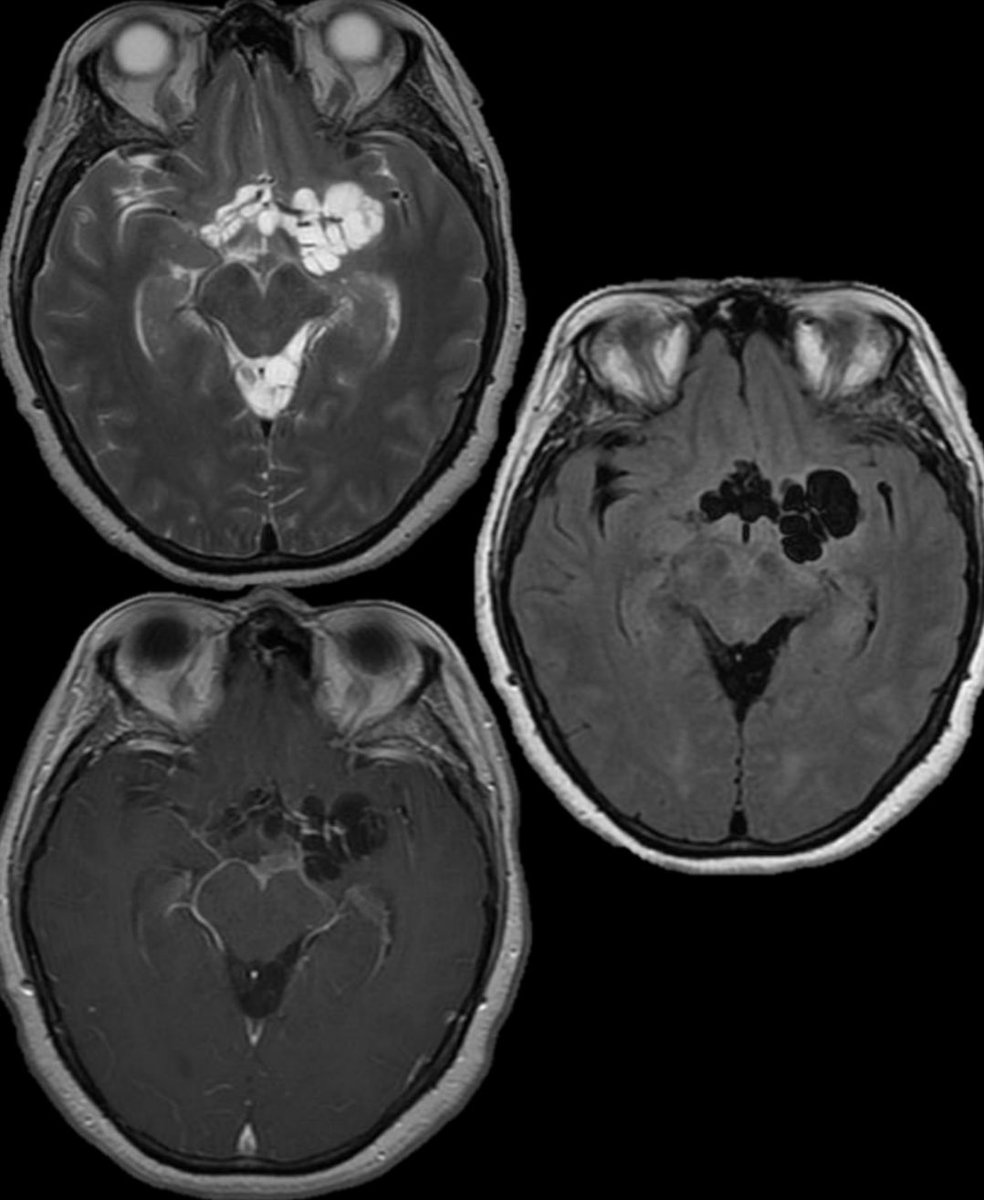

What is the most likely diagnosis in this 40 y/o F w/ subacute right lateral visual field defect? 🧠

#ent #neuroradiology #neurosurgery #radres #futureradres #MedEd